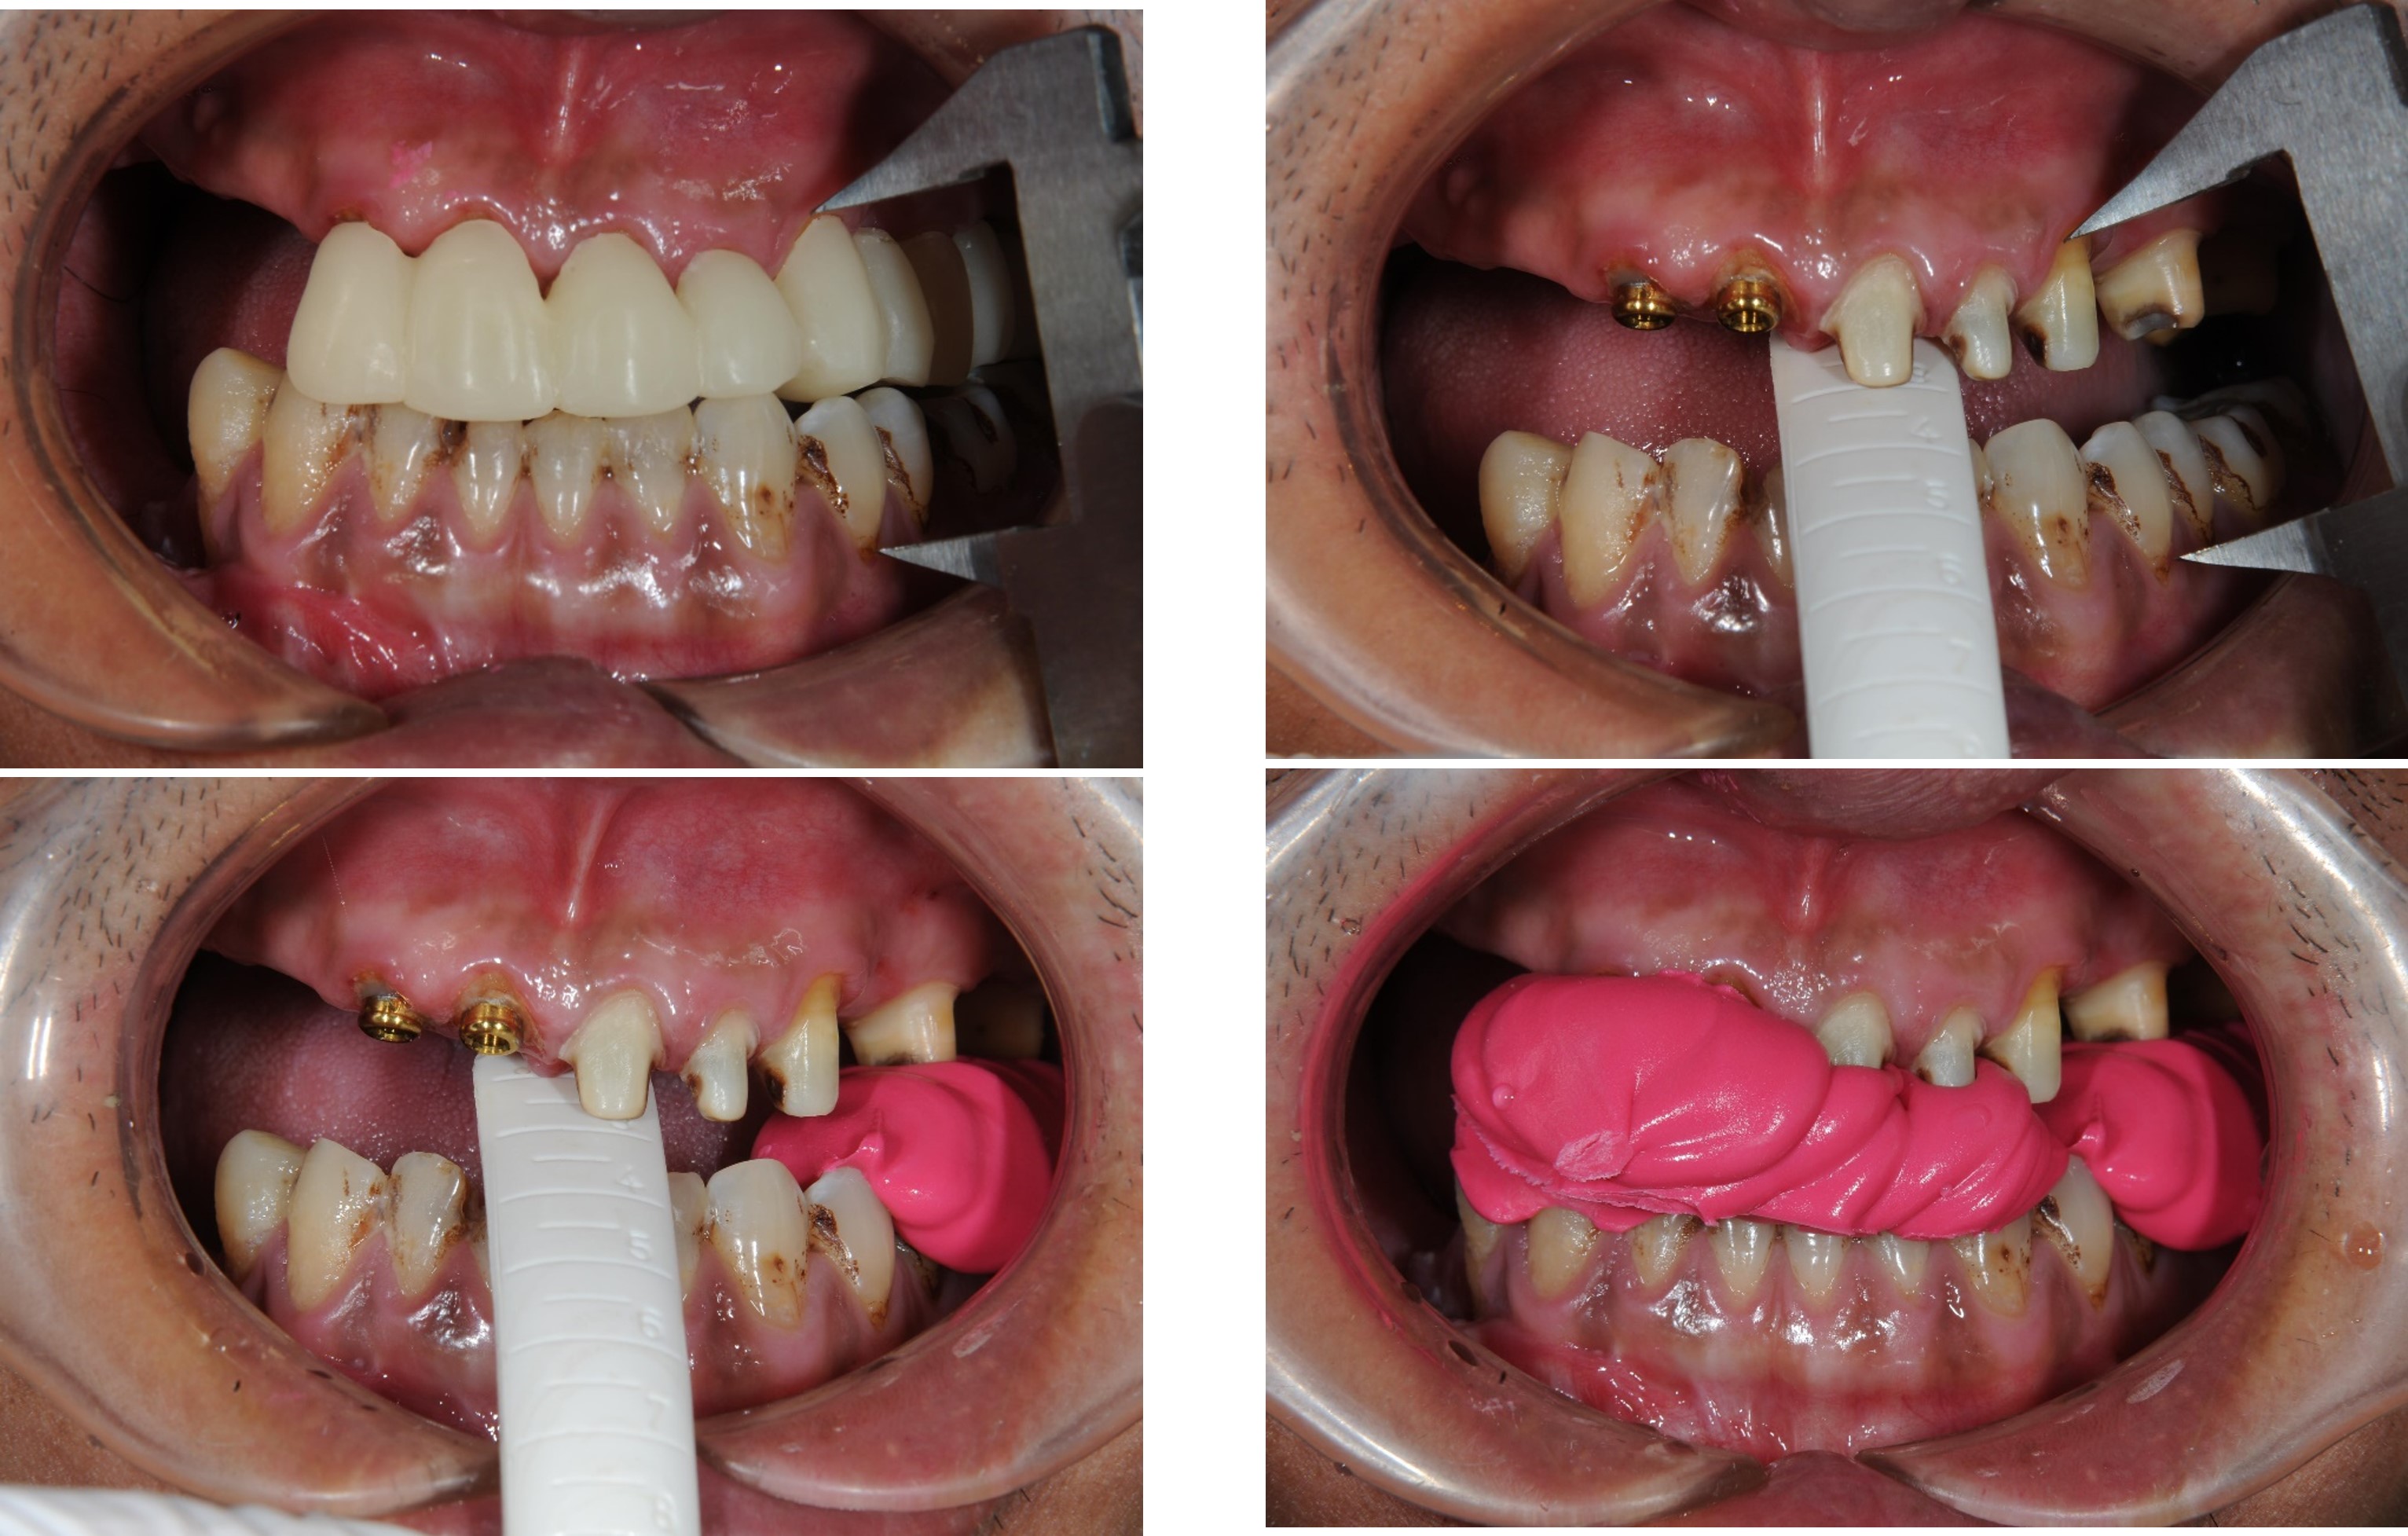

上下顎初步印模

咬合記錄